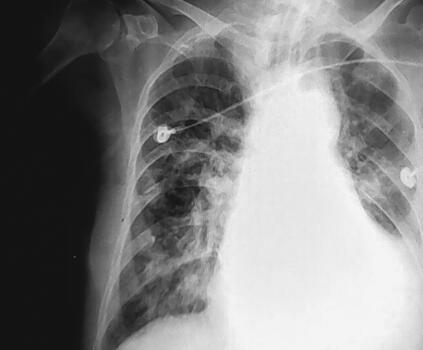

入院后立即气管插管,呼吸机辅助通气,心电、血压、氧饱和度监测,积极控制感染:头孢唑肟2.0g,每12小时1次;解痉、化痰,改善通气,改善心功能,强心、利尿、硝酸酯类扩血管治疗。经呼吸机治疗,很快意识好转,但是心功能没有明显恢复,心肌标志物检查一直在升高,TnI最高在33.8μg/L,BNP最高在17807pg/ml,呼吸机撤机困难,在呼吸机给予SIMV方式后出现急性左心衰竭,心源性休克,血压降至71/39mmHg,立即给予血管活性药物调整血压。4月10日患者体温开始升高,双肺痰鸣音增加,痰量增加,并为黄痰,胸部X线片见图2,痰涂片为革兰阳性球菌,革兰阴性球菌和革兰阳性杆菌,痰培养多次为鲍曼不动杆菌,属多重耐药型。经调整抗生素后体温逐渐好转,痰量减少,同时血中WBC在10×109/L左右,而且逐渐下降,中性粒细胞75%左右,逐渐准备撤机,胸部X线片见图3。但是患者在撤机过程中多次发作心力衰竭,出现咳粉红色泡沫样痰,同时血BNP指标逐渐上升,最高达45445.4pg/ml。4月17日将呼吸机调为机控A/C方式后逐渐好转。于4月29日行气管切开术。此时痰培养汇报均为鲍曼不动杆菌和铜绿假单胞菌,体温在38℃左右,双肺仍有大量痰鸣音、湿啰音,胸部X线片见图4,心率102次/分,血BNP 11969.6pg/ml,WBC 9.23×109/L,N 77.41%,根据药敏结果更换抗生素为头孢哌酮-舒巴坦钠3.0g,每8小时1次,联合口服米诺环素100mg,每天2次治疗,患者体温逐渐恢复,心率下降至60次/分左右,症状逐渐缓解(胸部X线片见图5)。血BNP降至6995pg/ml。但是呼吸机一直不能撤离。在抗感染的同时一直给予扩血管、利尿、改善心肌血供、改善心功能治疗,给予米力农、心钠素治疗,心力衰竭症状明显缓解,但是撤机仍然困难。终因高龄,全身状态差,出现尿路感染。尿培养、痰培养多次出现念珠菌生长(光滑念珠菌为主),尿中出现屎肠球菌生长2次。肾功能逐渐下降,血Cr最高至114μmol/L。并出现高热,白细胞升高,贫血(胸部X线片见图6)。将抗生素改为美罗培南加利奈唑胺及伏立康唑,症状逐渐改善,肾功能恢复正常,血常规正常,体温恢复正常。

图3 炎症有所吸收,但出现少许胸腔积液